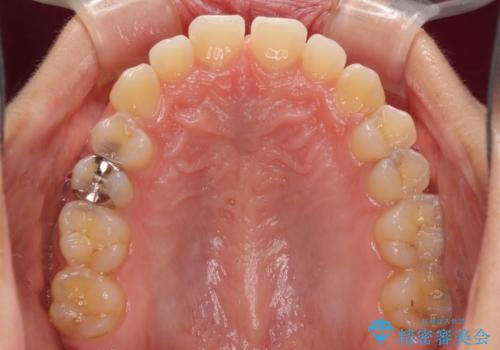

下の前歯が上の前歯を突き上げるように咬合するため、咬み合わせの位置を改善しながら隙間を閉じていきました。

元々の歯並びが悪くなかったため、9ヶ月で綺麗に仕上がりました。

すきっ歯は後戻りを起こしやすいため、上下ともに歯の裏側を細いワイヤーで固定した上で、リテーナーのマウスピースを装着していただいています。